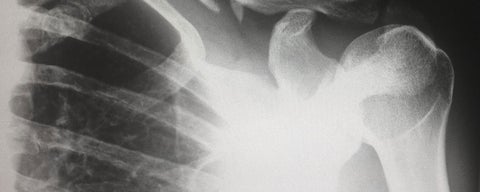

New medical imaging technology may transform osteoarthritis assessment

Dr. Nikolas Knowles, a researcher in Kinesiology and Health Sciences, is studying a new imaging technology to assess shoulder osteoarthritis.

Osteoarthritis researcher receives Canada Foundation for Innovation grant

Kinesiology professor Nikolas Knowles receives a Canada Foundation for Innovation John R. Evans Leaders Fund for his project to help slow or prevent joint deterioration from osteoarthritis.